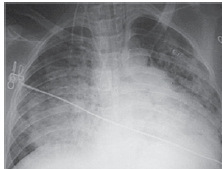

Homem de 62 anos, com história de insuficiência cardíacagrave, é internado devido um quadro dispneico. Pressão arterial: 140 x 115 mmHg, pulso: 122 bpm; ausculta pulmonar: crepitações até ápices bilateralmente. Radiografia de tórax é realizada e mostrada a seguir.

Em relação ao quadro clínico, é correto afirmar: